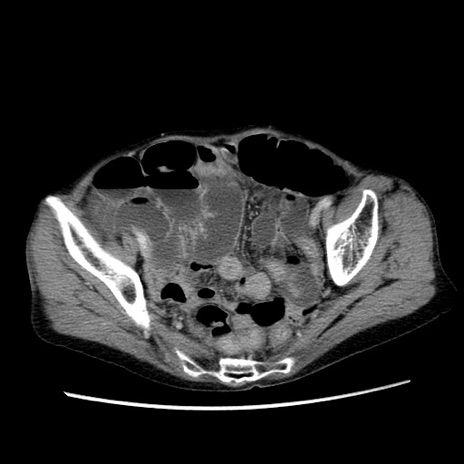

症例25(横断像)

【症例】80歳代女性

【主訴】胸のつかえ感

【現病歴】約9時間前に食後から胸のつかえた感じあり、嘔吐あり、来院。

【既往歴】胃癌(全摘)、胆摘、虫垂炎

【身体所見】心窩部に圧痛あり、反跳痛なし。

【データ】WBC 5700、CRP 0.05